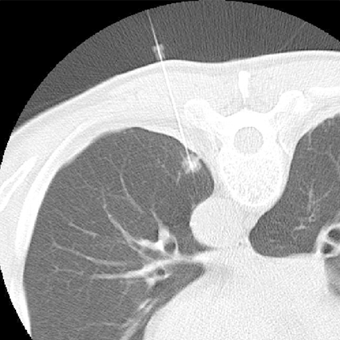

CTガイド下生検施行

1cmの肺結節にCT撮影しながら

生検針を穿刺し組織採取